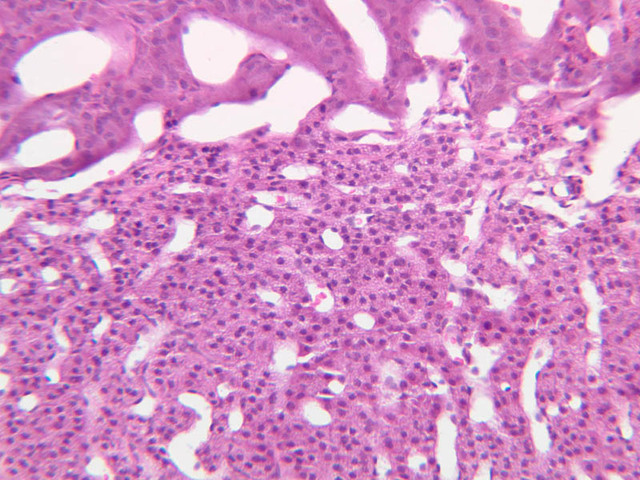

The adrenal gland (slide B-59, H&E [2.5x-labeled, 10x-labeled, 20x, 40x-labeled] [2.5x, 10x-labeled, 20x, 40x]; B-60, H&E [2.5x-labeled, 10x, 20x, 40x]; B-62, H&E [10x, 20x, 40x] [2.5x, 10x]) is a composite organ consisting of two functionally, structurally and embryologically different parts—an outer cortex and an inner medulla. Observe the gland at low power. Find the loosely organized tissue that comprises the medulla and the partially-separated columns of cells that make up the cortex. Scan the capsule and the tissue around it, looking for nerves and blood vessels. Study the pattern of cortical vasculature. In a pattern similar to that seen in the pars distalis of the pituitary, sinusoids run along the edges of columns or cords of cells. Owing to different arrangements of its constituent cells, the adrenal cortex has a layered appearance. From the capsule inward, these cortical layers are known as the zona glomerulosa, the zona fasciculata, and the zona reticularis.

The zona glomerulosa is located immediately beneath the capsule (B-60 adrenal gland, dog [10x, 20x] [20x, 40x]; B-59 [2.5x, 10x, 20x] [2.5x, 10x, 20x]). Its constituent cells are arranged in arcs or spheres, and, owing to their relatively small size, their nuclei appear to be close together. Cells of the zona glomerulosa secrete mineralocorticoids (e.g., aldosterone). The zona fasciculata consists of parallel columns or cords of cells that radiate toward the medulla and are separated by blood sinusoids (B-60 [2.5x, 10x, 20x, 40x]; B-62 [20x, 40x]). Owing to the extraction of lipids during histological processing, the cytoplasm of cells in the zona fasciculata appears highly vacuolated or "foamy". Cells of the zona fasciculata secrete glucocorticoids (e.g., hydrocortisone & cortisone) and some gonadocorticoids (weak androgens). The zona reticularis is the deepest cortical layer and lies adjacent to the medulla (B-60 [20x, 40x]; B-62 [20x, 40x]). It is characterized by irregular, interconnecting cords of cells which are separated by anastomosing capillary networks or sinusoids. Cells of the zona reticularis, which are smaller than those of zona fasciculata and do not contain as many lipid vacuoles, secrete gonadocorticoids and some glucocorticoids.